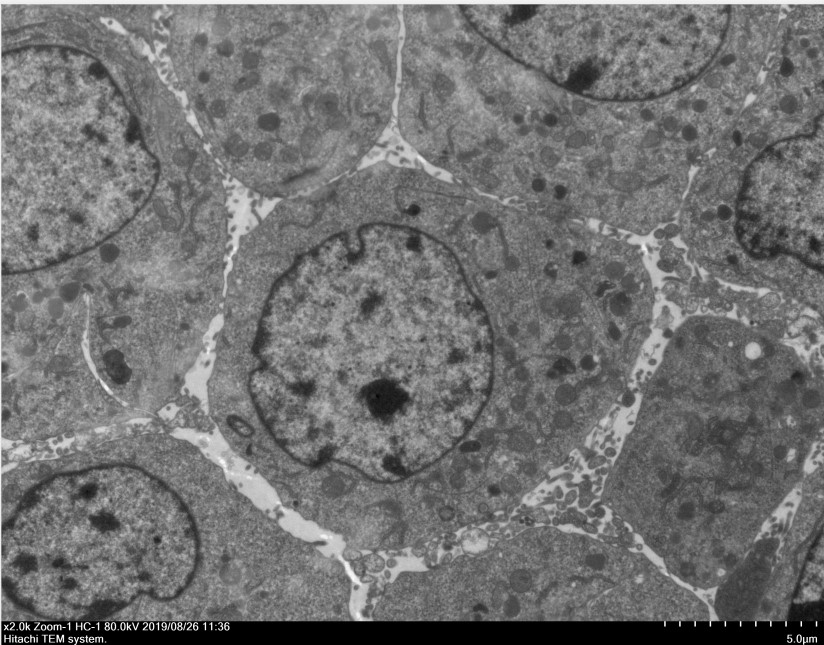

四、成果展示